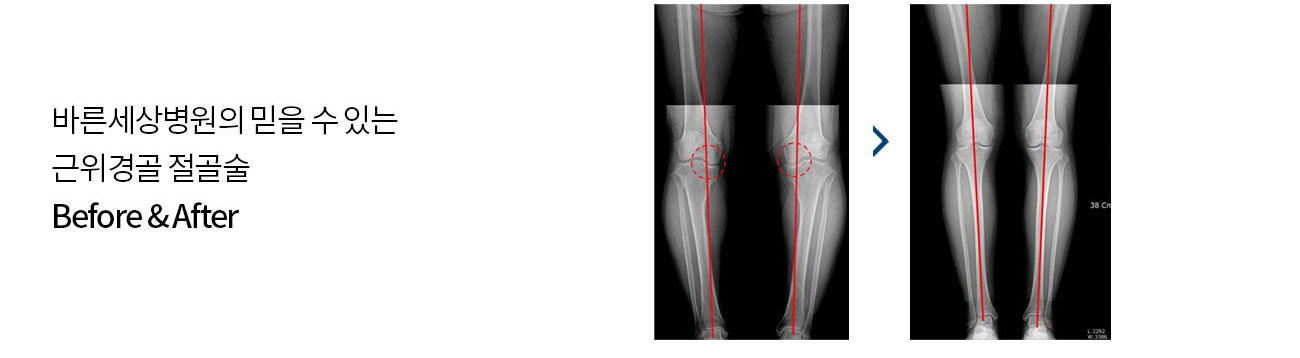

‘O’자형 휜다리를 곧게 교정해

퇴행성 관절염 치료, 만족도 높아

퇴행성 관절염이 악화되어 O 자형 다리로 변형되었을 경우 이러한 휜 다리를 바르게 고정하여 무릎 안쪽으로

집중되어 있는 무게를 외측으로 분산시켜 통증을 감소시키고 무릎의 뼈를 교정하는 수술방법입니다.

O자 다리를 바로 잡아 주어 미용적으로도 만족할 수 있습니다.